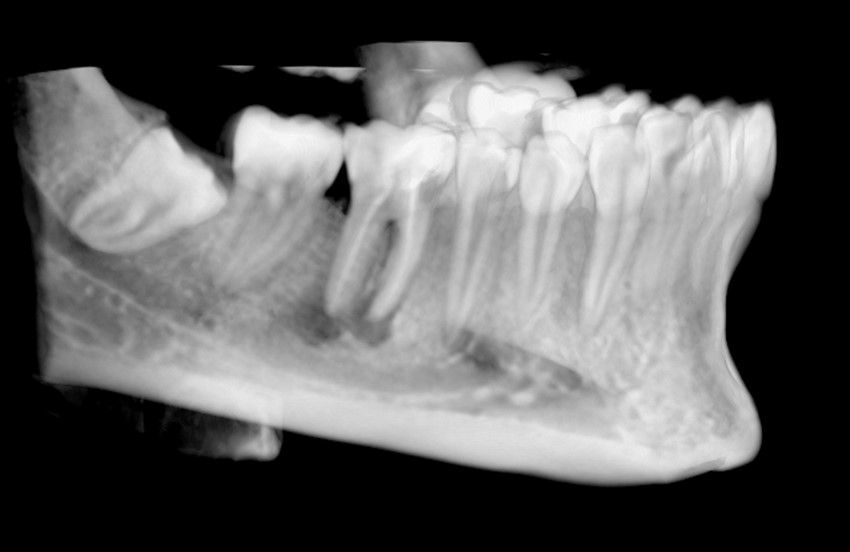

El sitio receptor debe garantizar la adaptación del diente donante, se realizará un diagnóstico mediante planificación con CBCT que permita segmentar virtualmente el diente donante y llevarlo digitalmente al sitio receptor3.

El diente donante ideal debería tener una anatomía radicular de fácil instrumentación endodóntica, y ápice abierto de al menos 1,5mm de diámetro para permitir una adecuada revascularización, con formación radicular de al menos 2/3. Así mismo, debería ser lo suficientemente pequeño para el asentamiento adecuado en el alveolo receptor, cónico, cuya extracción se pueda realizar de forma atraumática3,5,7.

Los dientes utilizados para realizar un AD más frecuentemente suelen ser de premolares a incisivo, de cordal a primer o segundo en pacientes jóvenes con ápice abierto. En adultos con ápice cerrado suele ser el autotransplante de cordal a primer o segundo molar3,4,6.